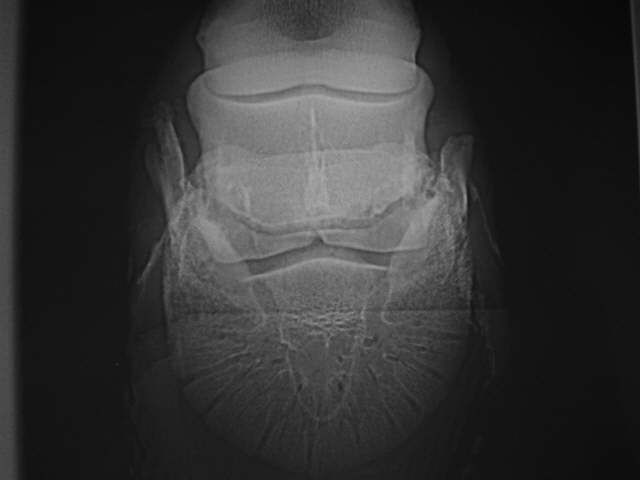

Hufknorpelverkn.

Neben massiven Zubildungen am Strahlbein links geringe Hufknorpelverknöcherung